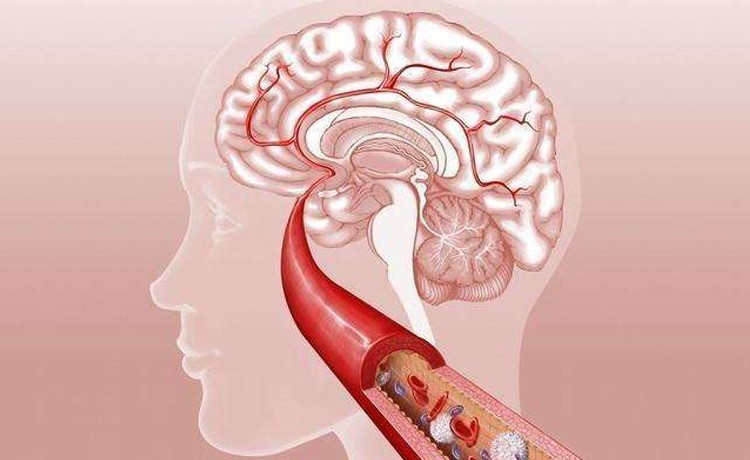

2、您有头痛、头晕、心慌、胸痛、胸闷、失眠、乏力、眼圈发黑等症状吗?

血毒通过血液循环进入全身的细胞、组织器官内,会直接破坏心、脑、肝、肾、皮肤等器官的正常功能,还会严重扰乱内分泌和新陈代谢功能,损害免疫系统与神经系统等,出现失眠、多梦、头晕、头痛、心悸、烦躁、易怒、忧郁等表现。

血管的寿命就是你的寿命,血毒就是罪魁祸首。因为血毒在血管堆积,并逐渐堵塞血管。人体的内脏、骨骼、肌肉、皮肤、毛发都是靠流动不息的血液来提供营养的。充满血毒的血液,像淤泥、像苔藓、像杂草、像油垢等,淤积在血管中,附着在血管壁上。当动脉血管堵塞70%时将发作心脏病、心肌梗死、心绞痛、脑中风、脑血栓等心脑血管疾病。